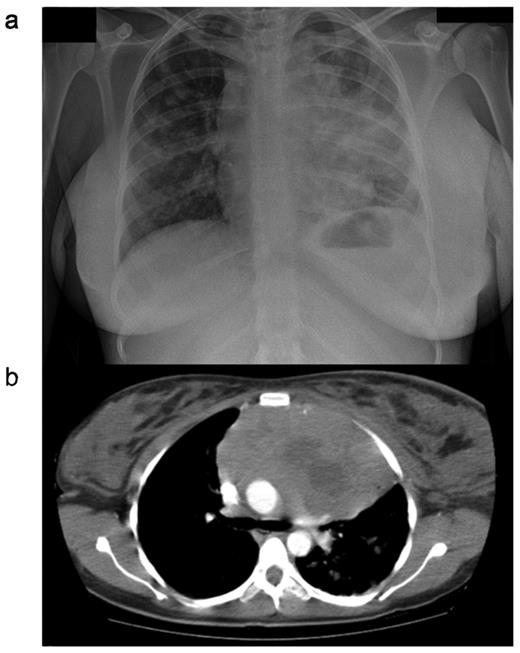

PMBL normally presents with a bulky tumor in the anterior mediastinum that is rapidly progressive and may give rise to local compressive effects including dyspnea, cough, dysphagia and superior vena caval obstruction4 (Figure 1 ). The disease affects females more frequently than men, and peaks in incidence in the third or fourth decades. This is in contrast to the more elderly population affected by DLBCL.5 Tumor extension is local, invading lungs, chest wall, pleura and pericardium, often resulting in effusions (Table 1 ). Breast edema is common and hoarseness may reflect recurrent laryngeal nerve damage. Because the local effects are seen early, most cases present when the disease is limited to within the thorax. Extranodal sites, however, may be involved, particularly at the time of disease recurrence, with a propensity for involvement of the kidneys, adrenals, liver, ovaries and central nervous system. Bone marrow infiltration at presentation is rare.

CXR (a) and CT (b) scan from a female patient presenting with primary mediastinal large B-cell lymphoma (PMBL). Note is the large anterior mediastinal mass, with areas suggestive of central necrosis. Marked breast edema is present.